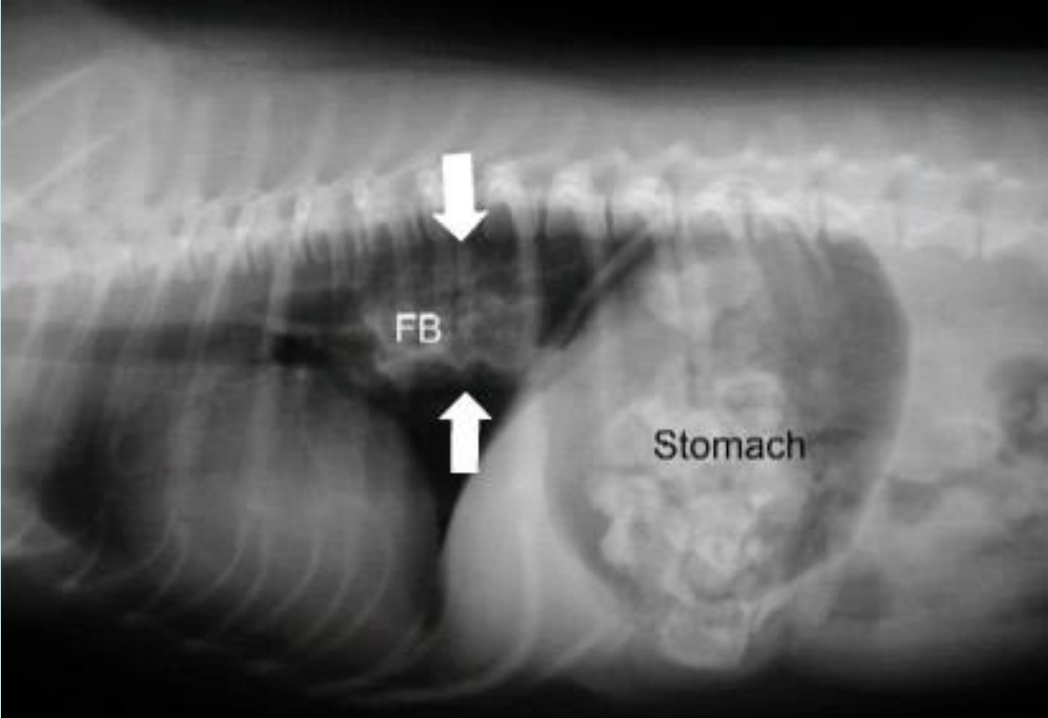

Esophageal Obstruction

common in young dogs

pawing at mouth, retching

prompt removal-endoscope, gastrotomy